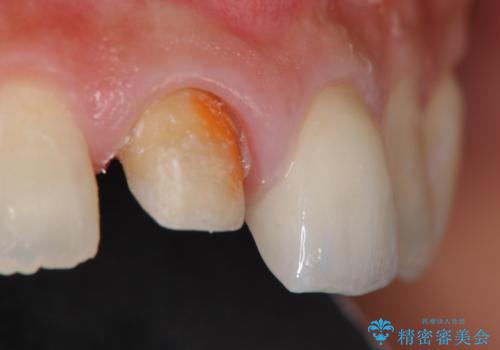

- 「 以前神経を取った歯の変色が気になる。前歯をきれいにして欲しい。」と治療を希望され来院されました。

目立つ上顎前歯に変色・大きな虫歯治療痕が見られ、審美障害を引き起こしています。

虫歯の徹底的な除去、根管治療を行いセラミック治療に入る前の環境をしっかりと整えたのち審美的なジルコニアセラミックで治療を仕上げました。